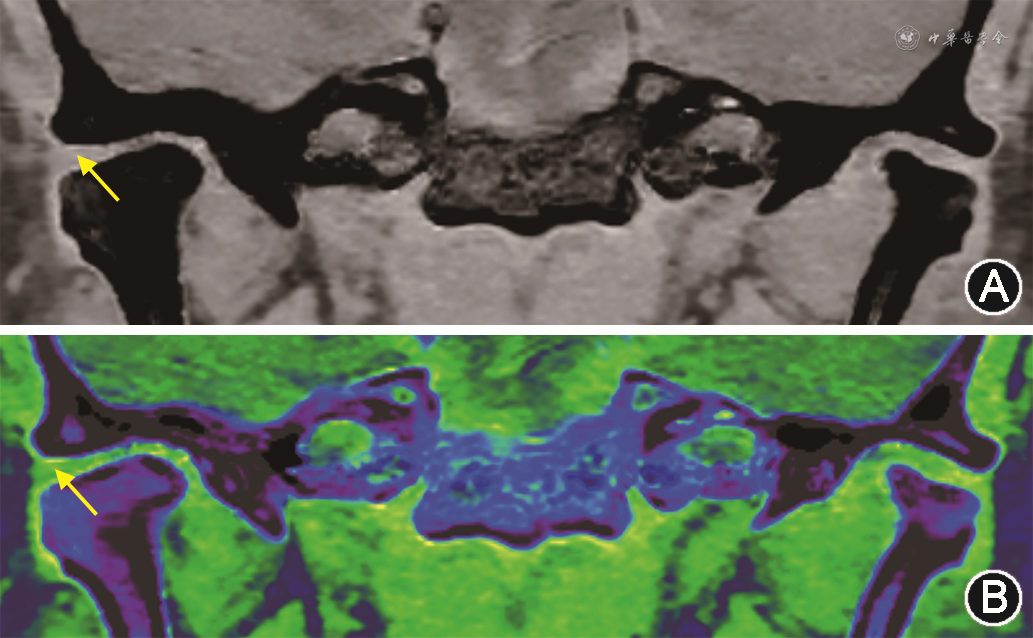

颞下颌关节盘由纤维组织(或纤维软骨)组成,含水量较少,因此在常规CT上表现为低密度而较难显示,在临床上通常采用MRI质子密度加权成像进行评估[21]。能谱钙抑制成像作为一种新的成像技术,通过虚拟去除周围骨性结构钙质成分,可清晰凸显关节盘的形态及位置[14, 15](图1)。

注:箭头示关节盘